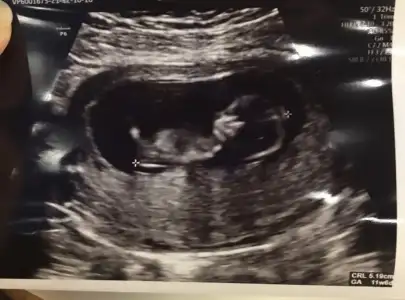

Geldimmm canım yolunda çok şükür her şey

5 gün ilerde çıktı yine.

Ense kalınlığı ve burun kemiği normal

İkili test yaptırmıyoruz feragat kağıdı imzaladık.

Oynuyordu ultrasonda

Cinsiyet tahmininde bulundu %51 kız

Tam yukarı çıkmamış o yüzden ilişki yasağı devam dedi

Bir de kullandığım folik asidi bıraktırdı başka ilaçlar verdi.